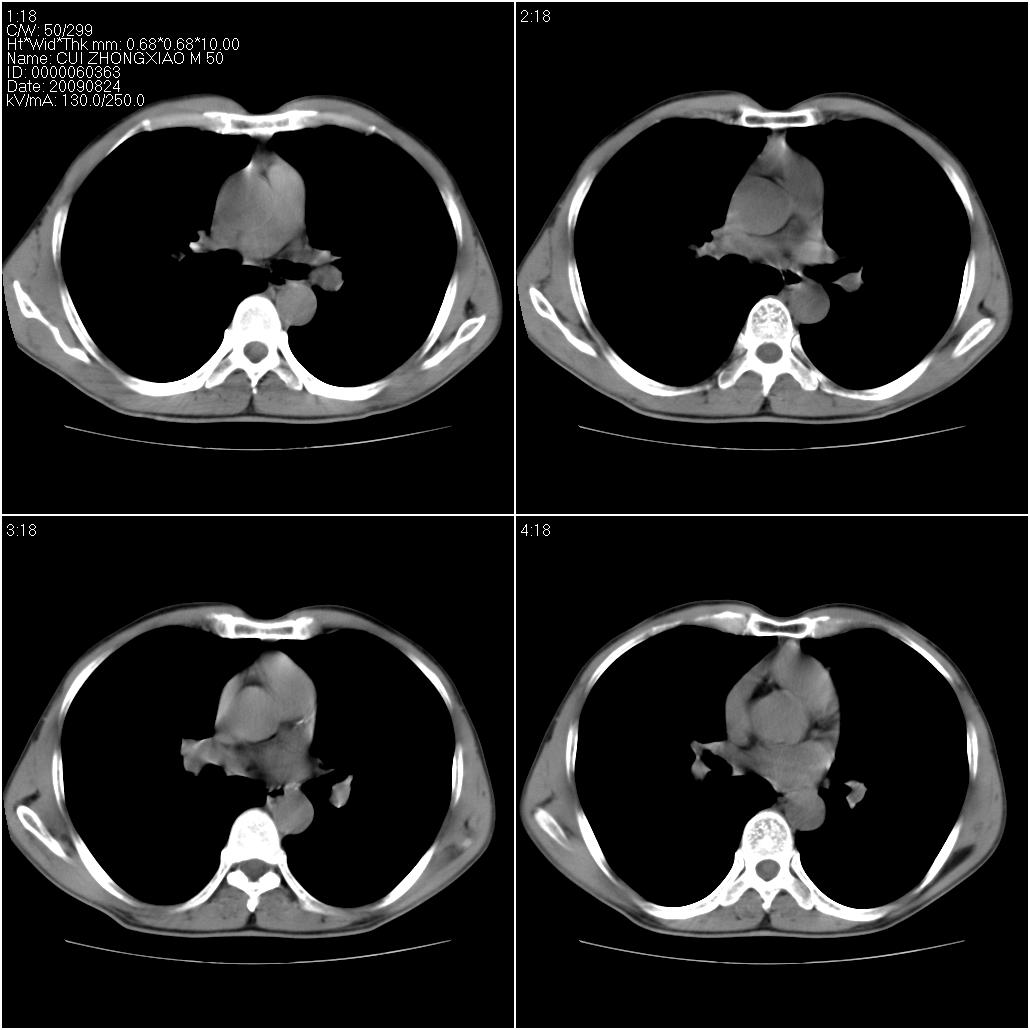

标题: CT21851:男性,50岁。间断性咳嗽半年。 [打印本页]

标题: CT21851:男性,50岁。间断性咳嗽半年。

磨玻璃样改变(左肺及右肺上叶前段),边缘模糊,考虑炎症,建议严格抗炎治疗后复查除外肺泡蛋白沉积症或肺泡出血(病人有咯血吗) 肺泡癌.

肝左叶肝内胆管扩张,进一步检查.

双肺磨玻璃征改变。。。支持楼上